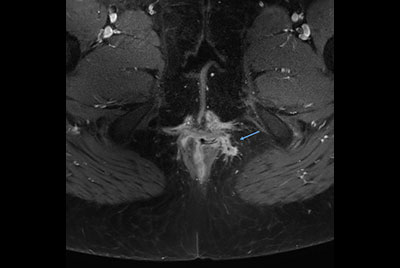

Pediatric pelvis with fistula